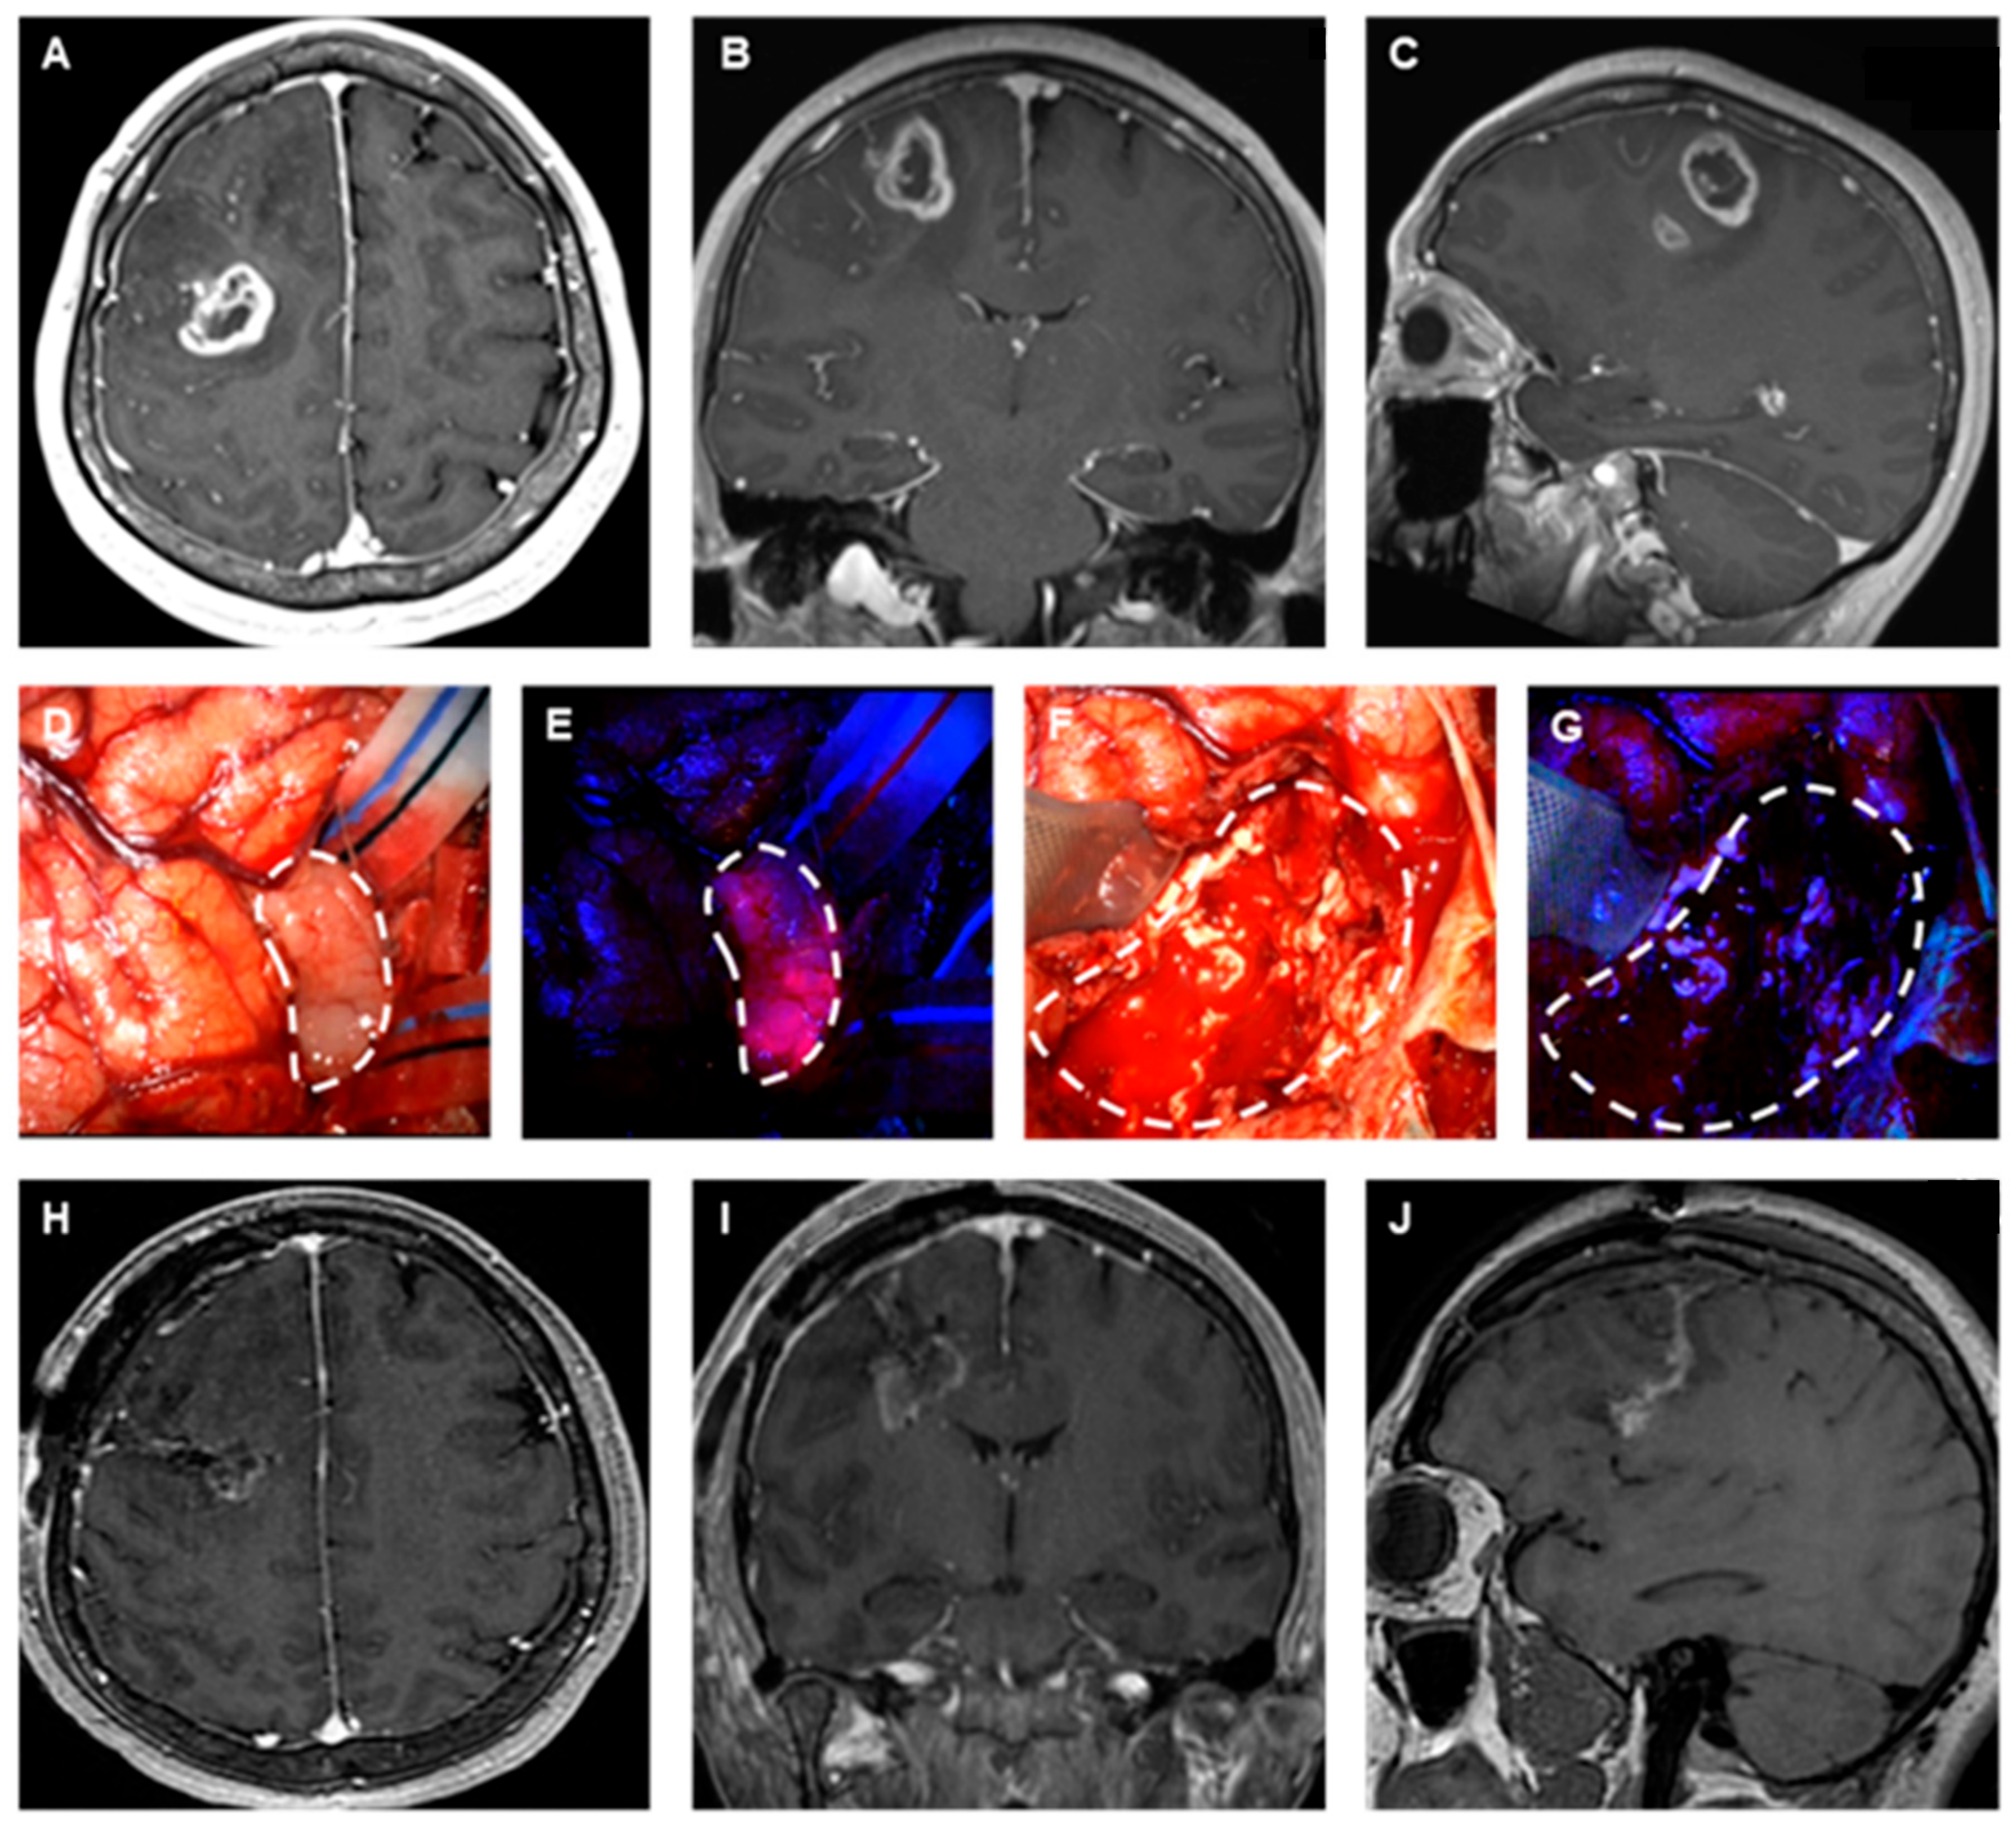

- Cho, S.S.; Salinas, R.; De Ravin, E.; Teng, C.W.; Li, C.; Abdullah, K.G.; Buch, L.; Hussain, J.; Ahmed, F.; Dorsey, J.; et al. Near-infrared imaging with second-window indocyanine green in newly diagnosed high-grade gliomas predicts gadolinium enhancement on postoperative magnetic resonance imaging. Mol. Imaging Biol. 2020, 22, 1427–1437. [Google Scholar] [CrossRef] [PubMed]

- Netufo, O.; Connor, K.; Shiels, L.P.; Sweeney, K.J.; Wu, D.; O’shea, D.F.; Byrne, A.T.; Miller, I.S. Refining glioblastoma surgery through the use of intra-operative fluorescence imaging agents. Pharmaceuticals 2022, 15, 550. [Google Scholar] [CrossRef]